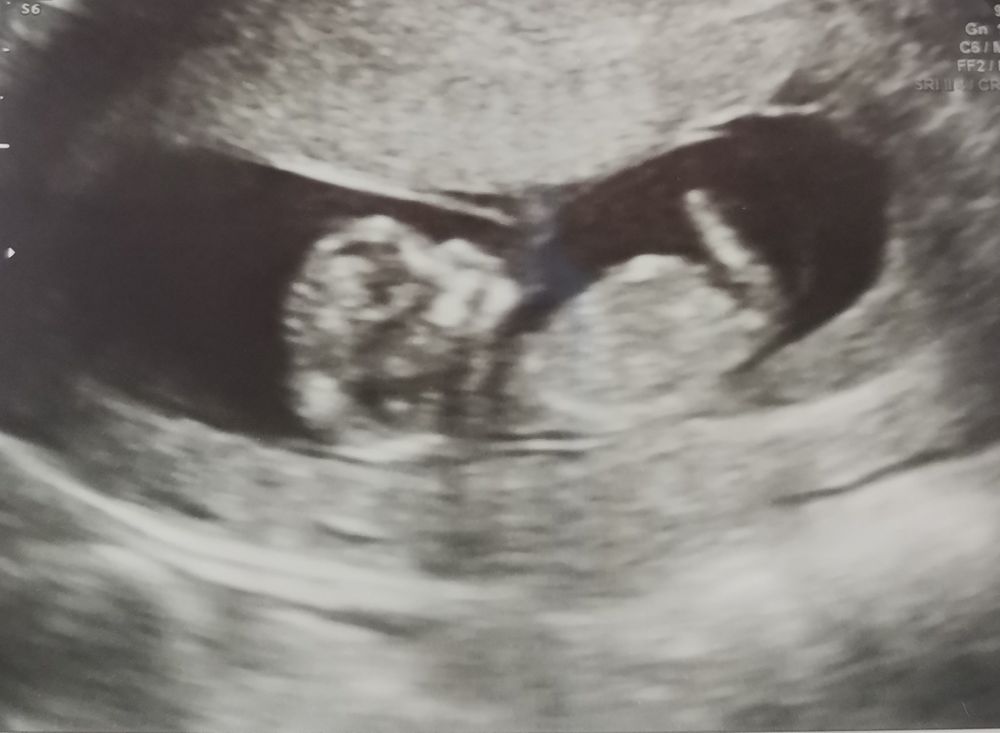

Пол ребёнка по узи

На этом фото половой бугорок прикрыт ножками) Я бы верила анализу)

Девочка 98%. Определяется по угла наклона лобковой кости, если параллельно бедру и спинке, девочка, если угол 45 градусов, мальчик, на мой взгляд у вас очевидно девочка, косточка параллельно спинке))

Анна, вы сами загуглите «наклон полового бугорка на узи» в картинках, и увидите )) девочка у вам будет)